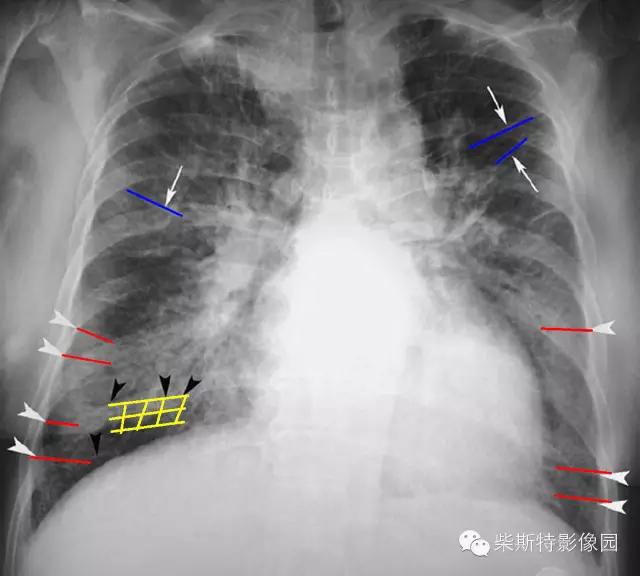

经典图像第二例:

大家找到克氏B线了吗?